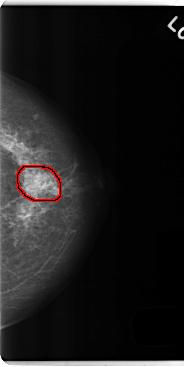

FILE: C_0186_1.LEFT_CC.OVERLAY

TOTAL_ABNORMALITIES 1

ABNORMALITY 1

LESION_TYPE MASS SHAPE IRREGULAR MARGINS ILL_DEFINED

ASSESSMENT 4

SUBTLETY 2

PATHOLOGY BENIGN

TOTAL_OUTLINES 1

BOUNDARY